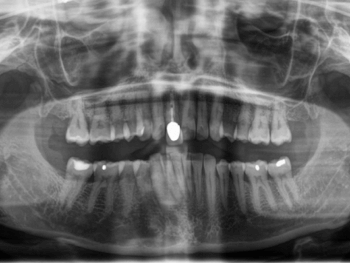

OPG nach Zahnunfall. 11 ist frakturiert.